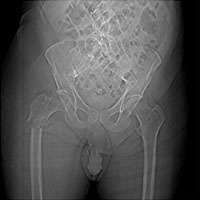

- Click on the image for a larger versionAScanogram. This patient with renal cell carcinoma shows a comminuted fracture of the proximal right femoral shaft.